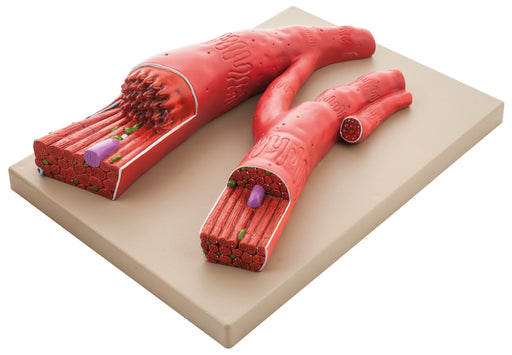

3 Piece Artery, Vein and Capillary Model Set, 13 Inch - Enlarged - Numbered - Cross Sections - Eisco Labs

3 PIECE SET || 3-dimensional model set includes enlarged artery, vein and capillary models showing cross-sections and interior structures FEATURES...

View full detailsAM16038 -